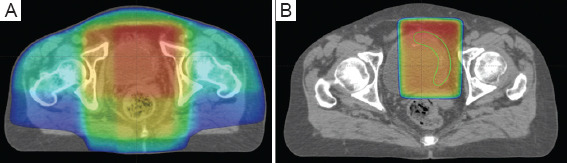

Abstract Image